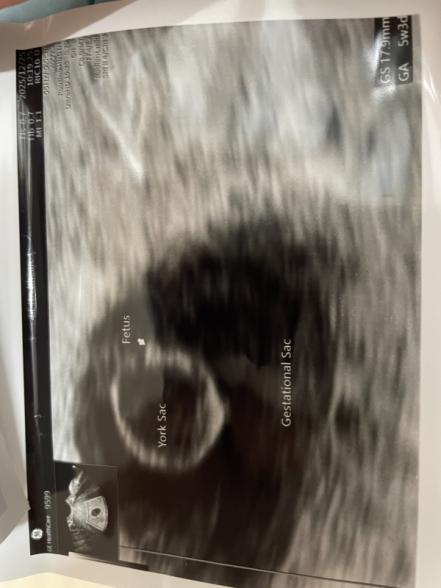

胎嚢と卵黄嚢は5w5dの時に見えました。

今までの流産と違い、胎嚢は9.3㍉あり、初めて先生に小さいね。と言われませんでした。

しかし、12/25の7w3dの妊婦健診の際に、何とか心拍を確認することは出来ましたが、胎芽が小さい。とのこと。

ピクピク心臓が動いているのは分かりましたが、胎芽は2ミリ程でした。